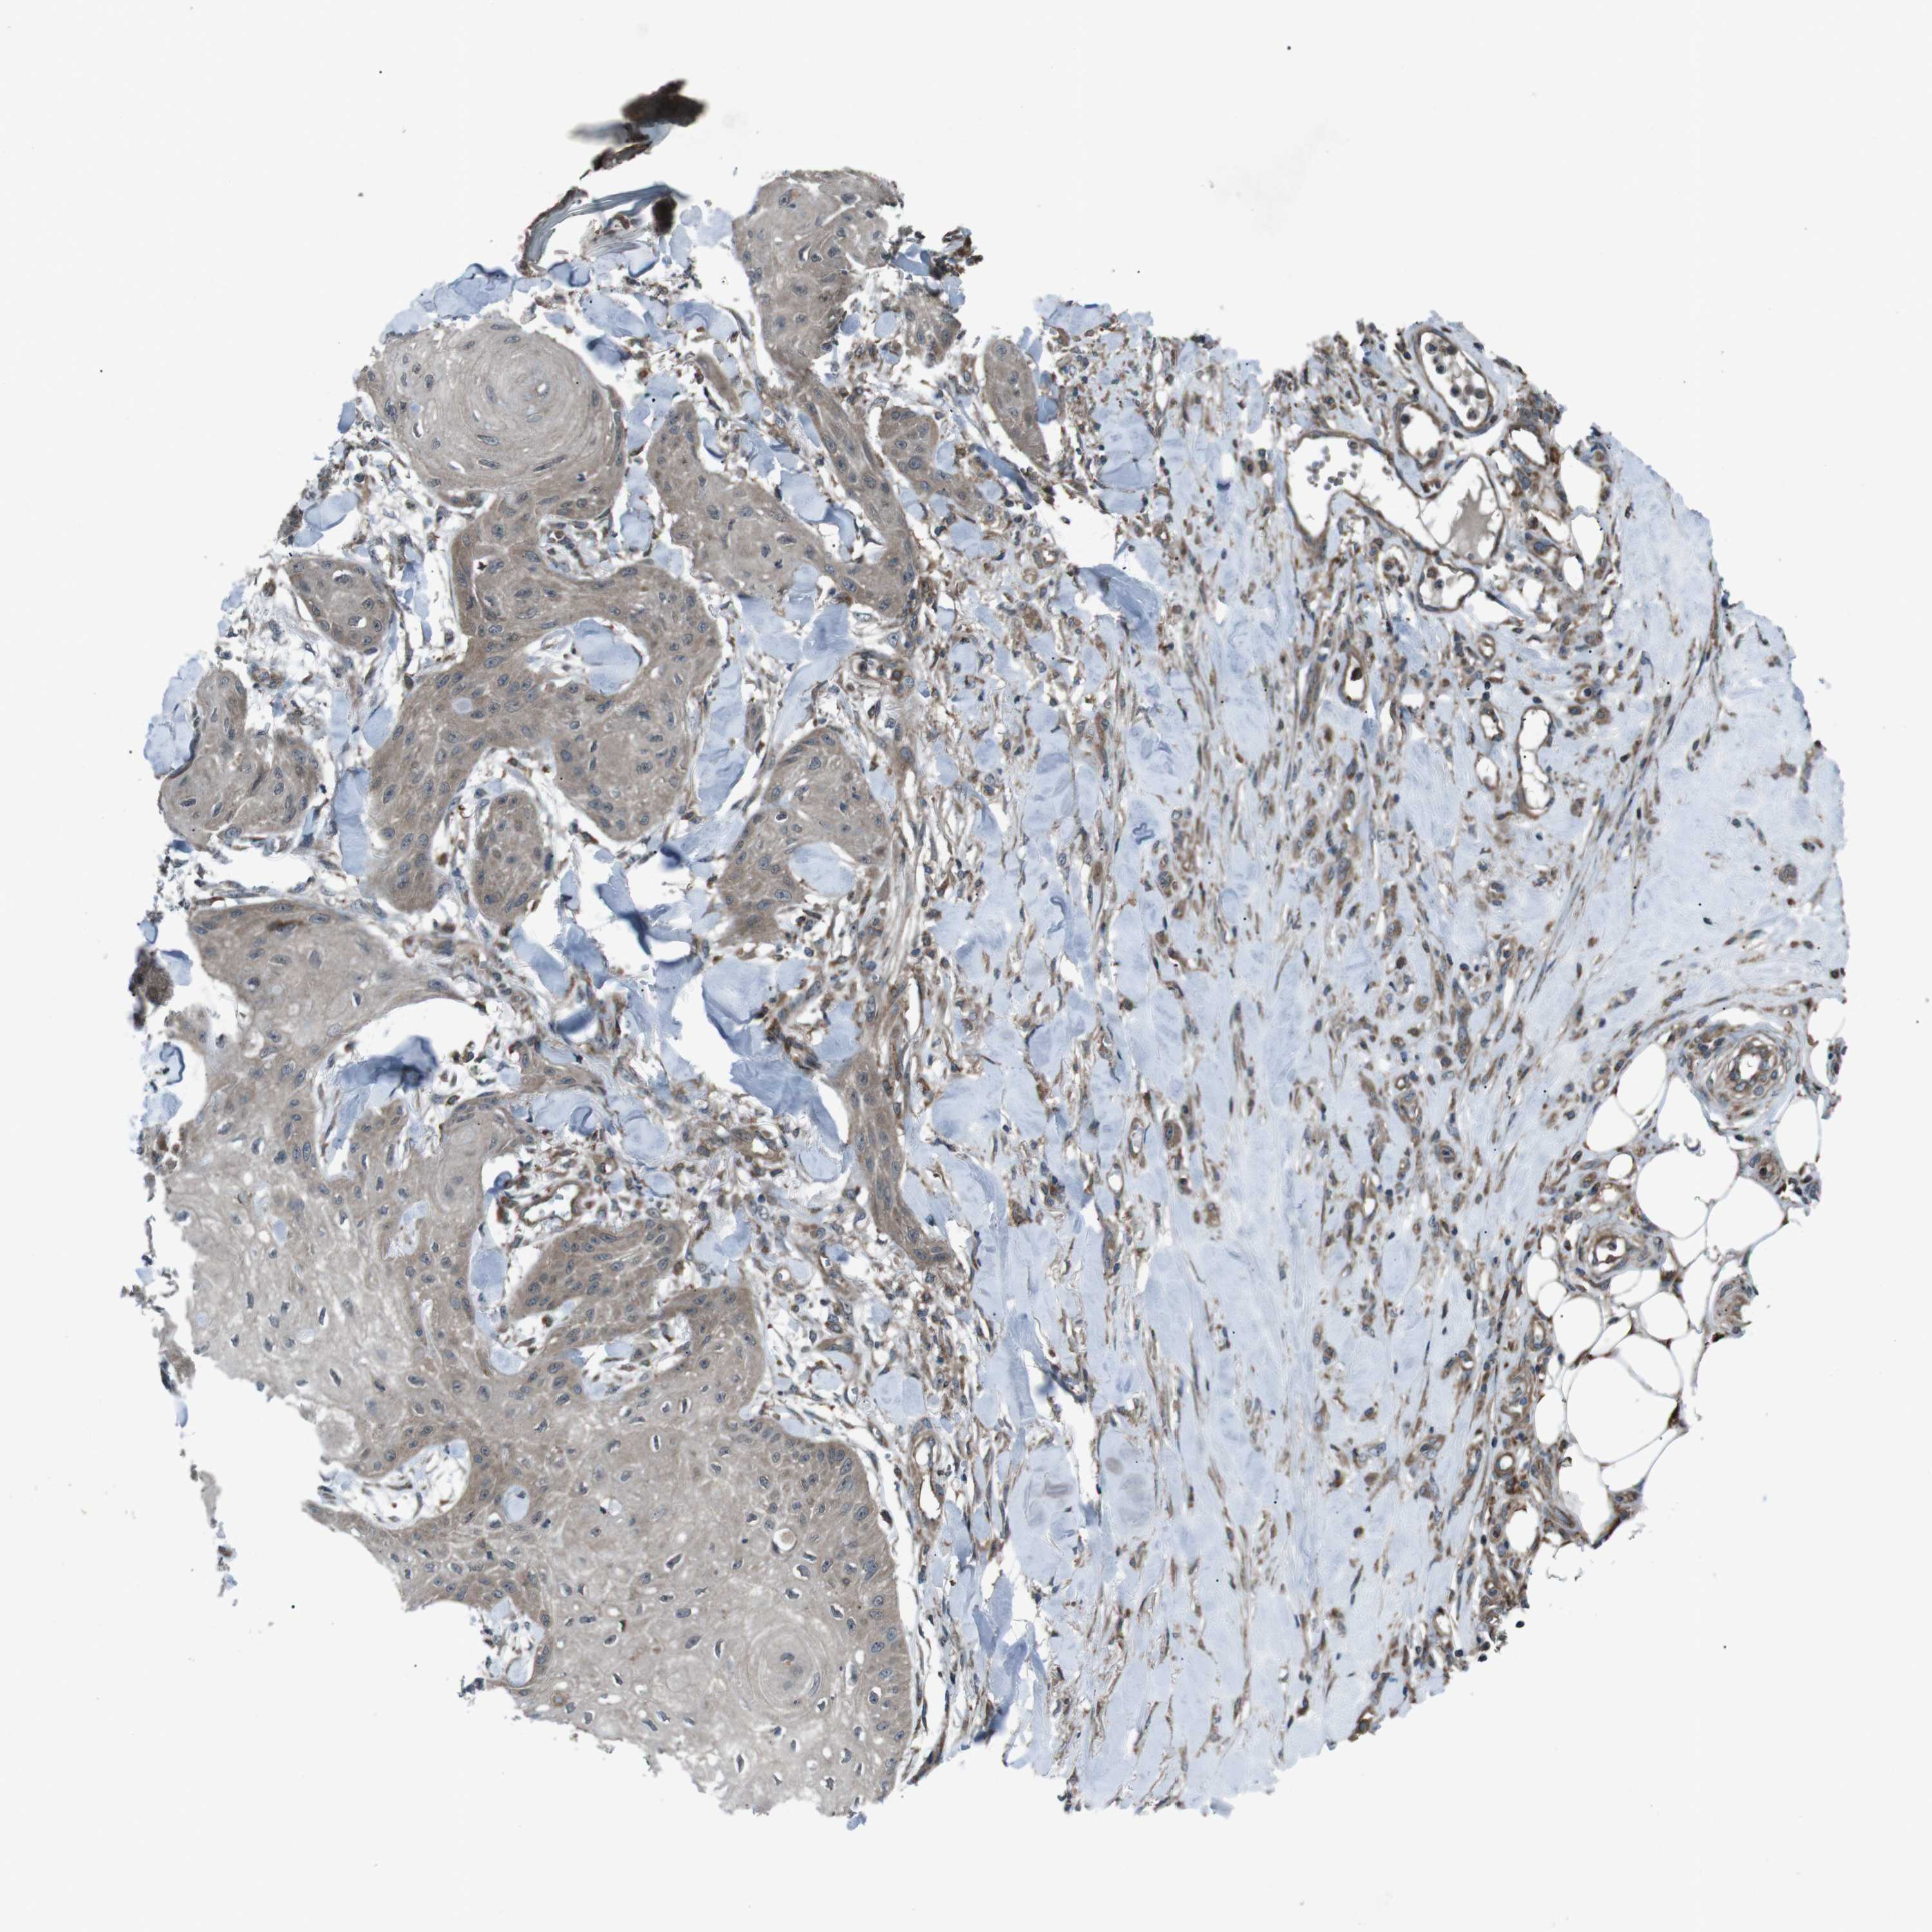

SKIN CANCER - Protein expressioni

A mouse-over function shows sample information and annotation data. Click on an image to view it in a full screen mode. Samples can be filtered based on level of antibody staining by selecting one or several of the following categories: high, medium, low and not detected. The assay and annotation is described here.

Antibody stainingi

Antibody staining in the annotated cell types in the current human tissue is reported as not detected, low, medium, or high, based on conventional immunohistochemistry profiling in selected tissues. This score is based on the combination of the staining intensity and fraction of stained cells.

Each image is clickable and will lead to virtual microscopy that enables deeper exploration of all samples and also displays staining intensity scores, fraction scores and subcellular localization as well as patient and tissue information for each sample.

Antibody CAB009771

Basal cell carcinoma